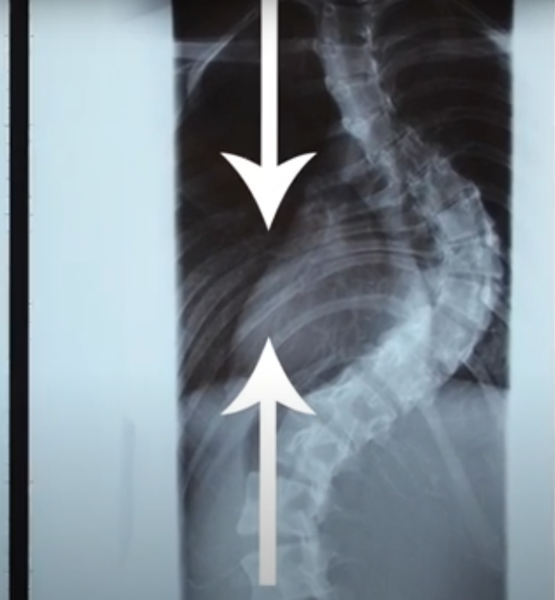

Рентгенограмма показала, у пациента идиопатический S-образный сколиоз 4-ой степени, деформация составляет 95 градусов.

Рентгенограмма показала, у пациента идиопатический S-образный сколиоз 4-ой степени, деформация составляет 95 градусов. Произошло смещение рёбер, одно ребро лежит на другом, из-за чего сдавливается полость лёгких.